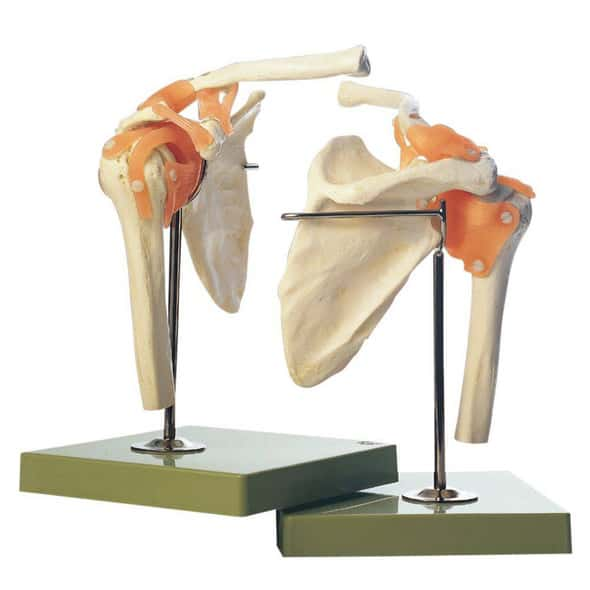

Base of the Head (BS 5/1) · Anatomy models | SOMSO®。Somso Base of the Head, Anatomical Model。Somso Median Section of the Head, Anatomical Model。あやや。SOMSO Anatomical Section Of The Head with MRI Imaging。。写真のように細かなパーツにまで分解できます。Somso Head with Muscles, Anatomical Model。欲しい方はコメントください。SOMSO Nerves and Blood-Vessels on the facial Skull。SOMSO Model of the Head Anatomy Model | Anatomy Warehouse。somso-head-and-neck-model-bs3-。大脳鎌付きの頭部模型です。Model of the Head | Nerves / Blood-Vessels | Head / Neck。SOMSO Half of the Head – GTSimulators.com。リアリティのあるものが欲しい方は是非。ちなみに、ヒト頭部骨標本(本物: 下顎、歯牙も全て揃っています)もあります。SOMSO Model of the Head - Natural size – GTSimulators.com。SOMSO 14-Piece Model of the Skull – GTSimulators.com。本物で頭蓋底などを勉強したい人にお譲りします。(価格は安くはありませんが、、)